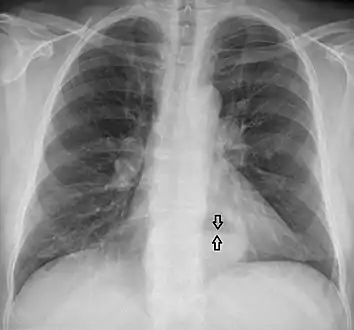

Diagnosis

The diagnosis of a hiatal hernia is typically made through an upper GI series, endoscopy, high resolution manometry, esophageal pH monitoring, and computed tomography (CT). Barium swallow as in upper GI series allows the size, location, stricture, stenosis of oesophagus to be seen. Besides, it can also evaluate the oesophageal movements. Endoscopy can analyse the esophageal internal surface for erosions, ulcers, and tumours. Meanwhile, manometry can determine the integrity of esophageal movements, and the presence of esophageal achalasia. pH testings allows the quantitative analysis of acid reflux episodes. CT scan is useful in diagnosing complications of hiatal hernia such as gastric volvulus, perforation, pneumoperitoneum, and pneumomediastinum.[8]